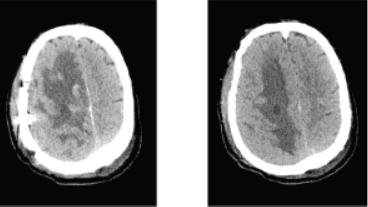

头部额叶间变型孤立性纤维性肿瘤/血管外皮细胞瘤1例报道

病史摘要:67岁男性患者,主诉头痛伴左侧肢体无力4天,无头晕、呕吐等其他症状。无相关既往史提及。诊疗过程:当地医院头部CT提示右侧顶叶脑出血,MRI示右侧额叶混杂信号占位伴出血。入院后复查头颅增强CT考虑肿瘤性病变合并出血,初步诊断为右侧额顶叶出血:瘤卒中?。术中见右侧额顶叶占位性病变,质地坚韧、血供丰富等。术后病理检查初诊为(脑)骨外尤文肉瘤/原始神经外胚叶肿瘤,后经华西医院病理

血管外皮细胞瘤

疑难